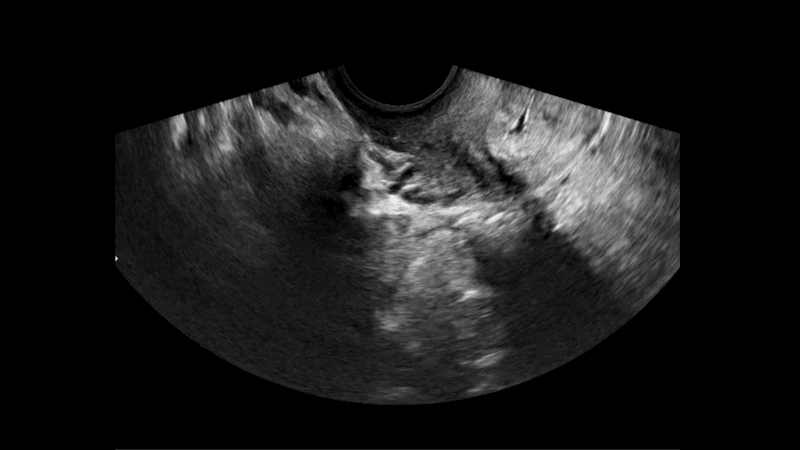

Folliscan automates identification and follicular measurement from 2D and 3D transvaginal ultrasounds, generating fast and consistent results that complement the specialist’s evaluation and reduce variability between clinical explorations.